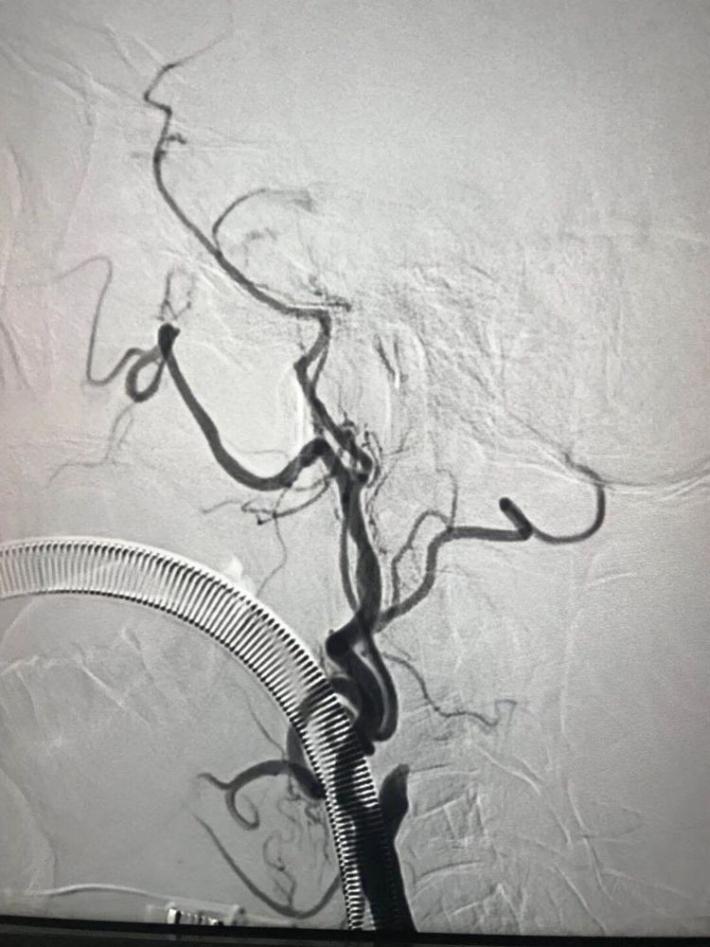

左侧肢体无力凝视意识模糊3小时来院。右大脑中动脉m1段慢性高度狭窄溃疡斑块基础上急性闭塞。

rtpa溶栓后桥接solitaireFR取栓再通,残余狭窄很重,gateway球囊扩张后血流维持不住,enterprise自膨支架植入,血流重建。